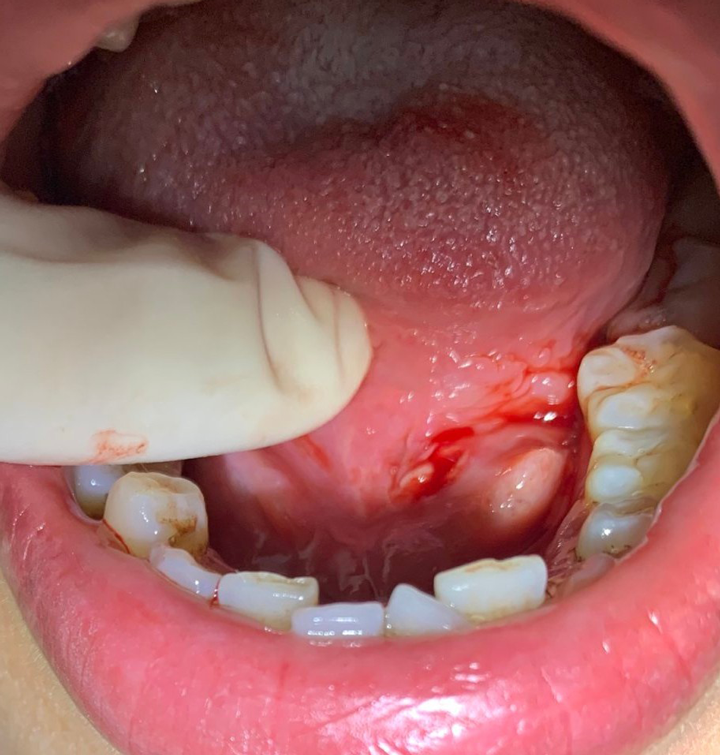

Quy trình khám viêm tuyến nước bọt mang tai thường bắt đầu bằng việc đánh giá triệu chứng lâm sàng, bao gồm cảm giác sưng và đau tại khu vực tuyến nước bọt. Để có cái nhìn rõ ràng hơn về tình trạng tổn thương, bác sĩ có thể chỉ định tiến hành CT scan hoặc MRI. Các hình ảnh này sẽ cung cấp cái nhìn chi tiết về cấu trúc và mô mềm của tuyến, giúp phát hiện bất thường nếu có.

Siêu âm cũng là một bước quan trọng trong quy trình này. Trước khi tiến hành, bệnh nhân không cần nhịn ăn mà chỉ cần nằm ngửa, gối dưới vai để tạo điều kiện cho quá trình siêu âm diễn ra thuận lợi. Nội soi có thể được sử dụng để quan sát trực tiếp bên trong các ống tuyến nước bọt, từ đó xác định rõ nguyên nhân gây viêm.

Ngoài việc thăm khám lâm sàng, bác sĩ có thể sử dụng ống nội soi để kiểm tra tình trạng của tuyến nước bọt. Điều trị viêm tuyến nước bọt thường bao gồm việc giảm sốt, giảm đau và chống viêm nhằm giúp người bệnh cảm thấy dễ chịu hơn. Nếu có nhu cầu, bác sĩ cũng sẽ chỉ định các loại thuốc cụ thể dựa vào căn nguyên của bệnh.